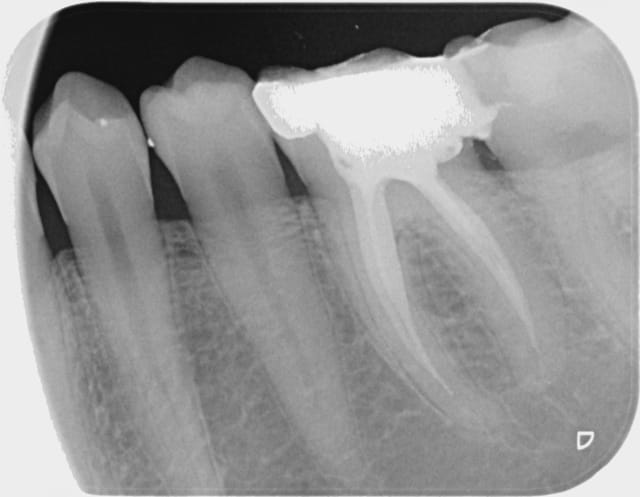

En ce moment j'ai pas vraiment le feu sacré en endo. que pensez vous de cette 36? Est ce que je retourne dans les canaux distaux pour gagner le dernier millimètre? vu que c'est un pote j'ai pas trop le choix...

tu as instrumenté jusqu'au bout et c'est juste l'obtu qui a foiré ou est ce que tu n'as jamais atteint le bout?

Si t'as instrumenté jusqu'au bout bien irrigué et que ce sont justes tes cônes de gutta qui te l'ont fait à l'envers (ça m'arrive aussi des fois, radio maitre cône impec, radio final il manque 1mm...) ben le pronostique reste bon et retrouver ta longueur sera facile si tu veux retraiter.

Si t'as pas réussi à aller au bout la première fois, ça risque pas d'être plus simple en retraitant... mais tu peux tjrs essayé si t'as la patate :D